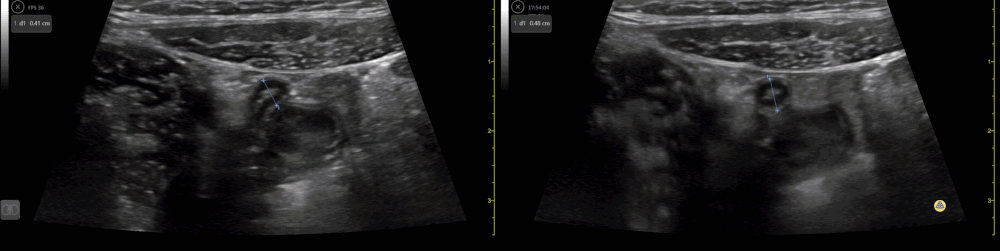

10 y/o with abdominal pain. Normal appendix identified medial to the iliac vessels. Contributor: Elena Chen, MD